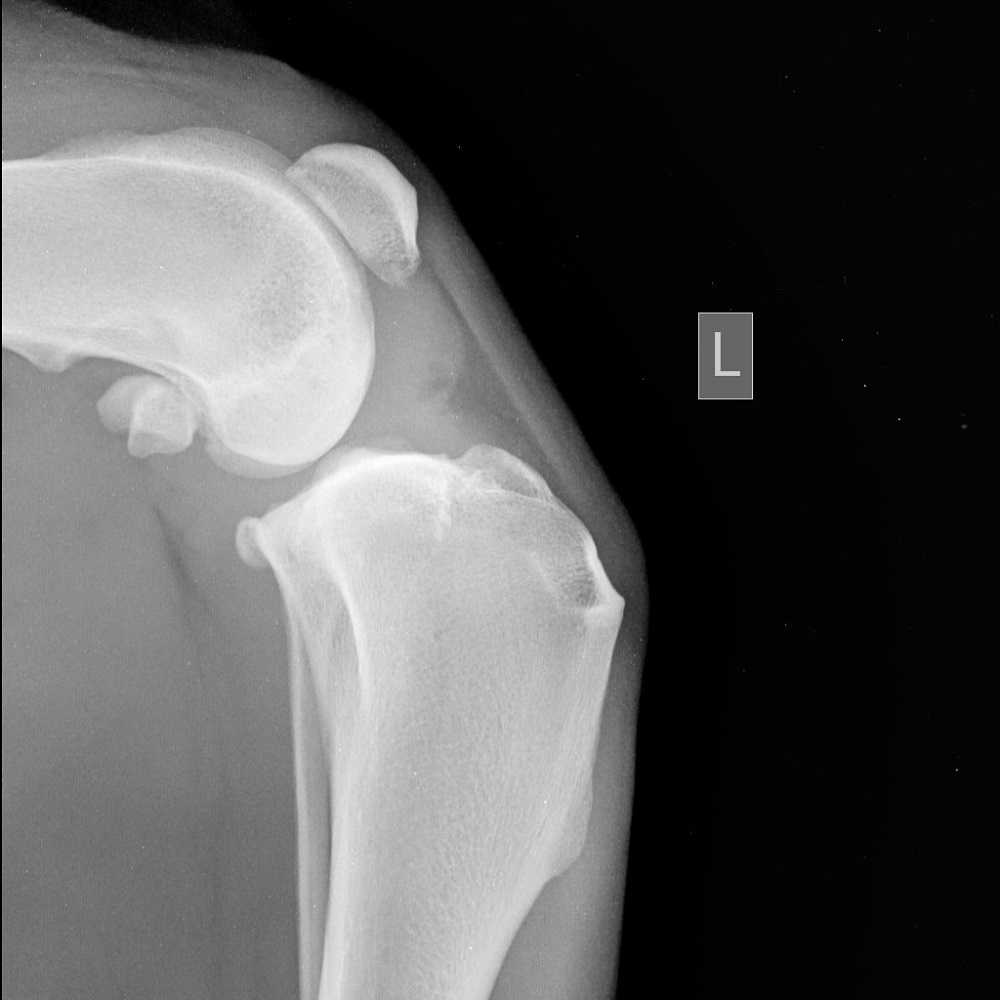

Боковая рентгенограмма при хроническом течении разрыва ПКС у алабая